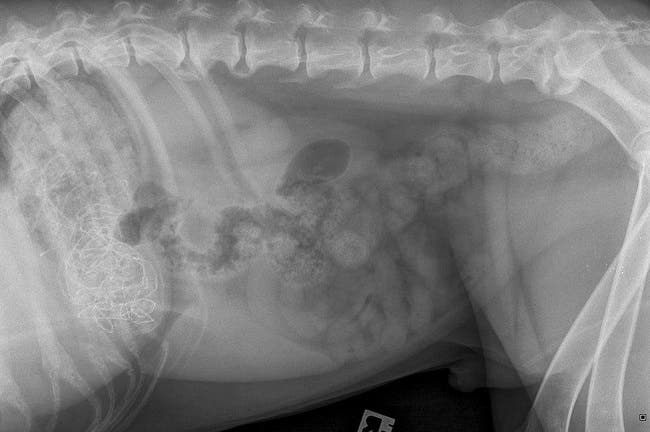

كاد كلب من فصيلة Great Dane أن يموت بعد تناوله زينة عيد الميلاد بطول ثلاثة أقدام (91 سم).

وتم نقل الكلب إلى الطبيب البيطري عندما أدرك أصحابه أن شريطًا من الزخرفة الاحتفالية مفقود من رف الموقد يوم الاثنين الماضي.

وأخذ العاملون في عيادة PDSA في مارغيت الكلب "دكستر" البالغ من العمر 10 سنوات مباشرة إلى الجراحة الطارئة بعد أن أكدت الأشعة السينية أن هناك شيئًا ما استقر في معدته.

وقالت الطبيبة البيطرية "كيت ميلروي": "كان من الضروري أخذ دكستر مباشرة لإجراء عملية جراحية طارئة، فمن الواضح أنه كان يسبب انسدادًا وسيكون قاتلًا إذا لم نقم بإزالته في أقرب وقت ممكن".

وتابعت: "هناك دائمًا بعض المخاطر في أي نوع من العمليات، ولكن بفضل مالك "دكستر" الذي لاحظ العلامات المبكرة للمشكلات، كنا نأمل أن يكون ذلك واضحًا".

وأردفت تقول: "لقد فوجئت جدًا عندما تمكنت من إخراج الزينة كقطعة واحدة بالرغم من ذلك".